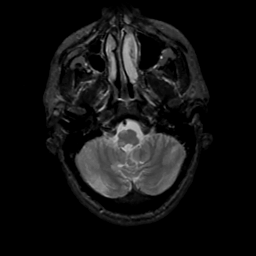

MR Study #8, March 31, 1991 -- Slice #8